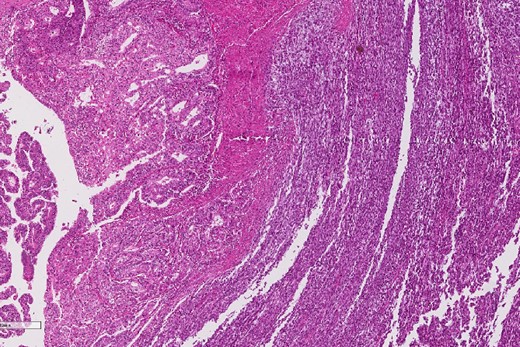

A review of the previously resected esophageal tumor revealed the presence of both epithelial and sarcomatous components. The epithelial component was composed of moderately to poorly differentiated adenocarcinoma, while the sarcomatous component showed hyperchromatic round to spindle cells with scant cytoplasm and frequent mitoses (Figs 3–6). The intrathoracic tumor showed a similar morphology as the sarcomatous component of the esophageal tumor, with focal rhabdomyoblastic differentiation (Fig. 7). The latter was strongly positive for desmin, myogenin, and MyoD1 and was focally positive for synoplastin, CD56, CD 10, and FL1.

Low power magnification of the esophageal tumor exhibiting the epithelial (left) and the sarcomatous components (right).